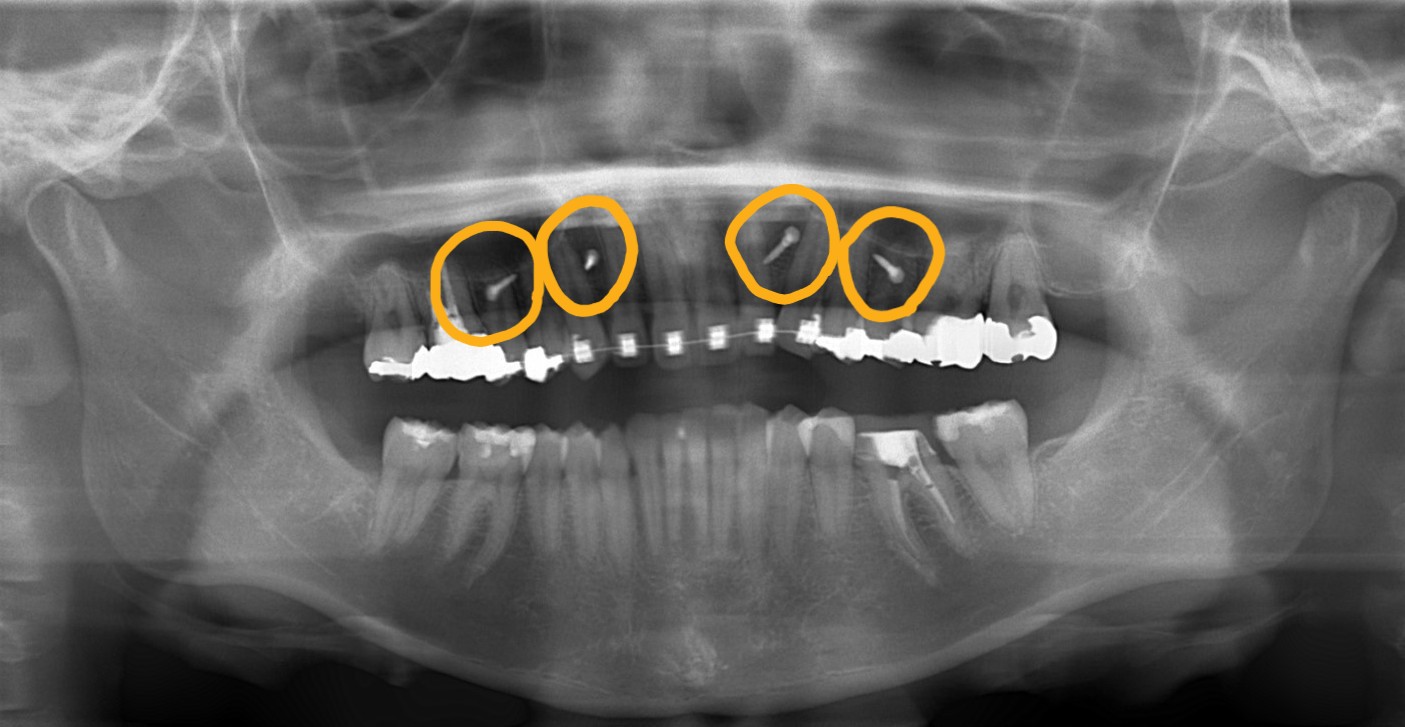

矯正後の状態をレントゲン写真で確認すると、

【治療装置】 スタンダードtypeのマルチブラケットシステム、

アンカースクリューを計6本

PLAS & パラタルバー